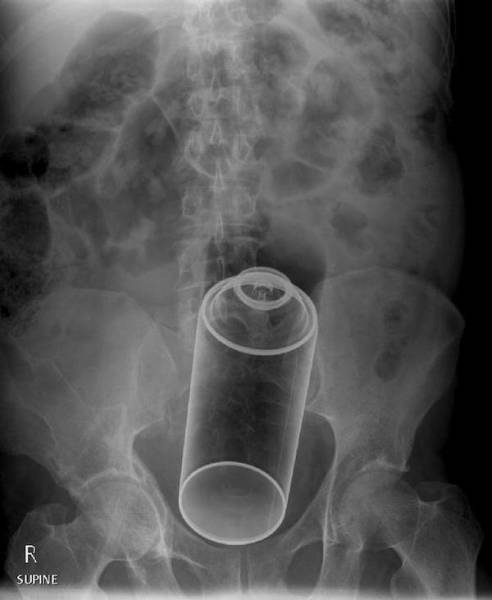

An aerosol can.